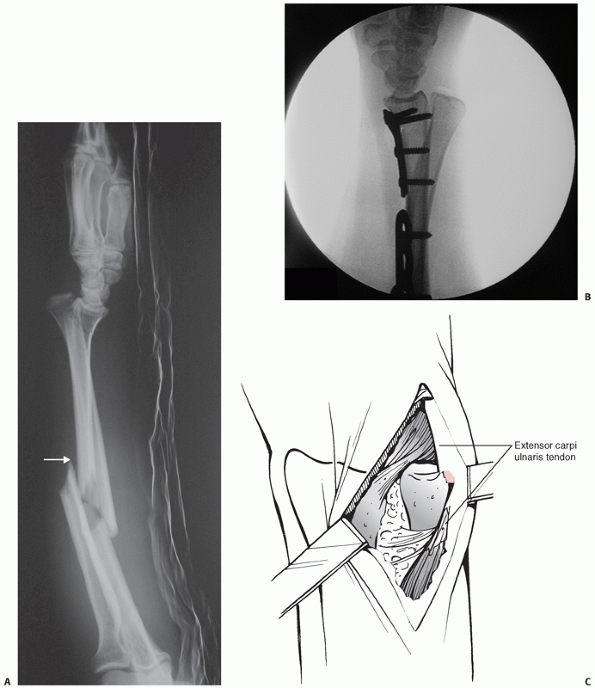

Frequently, there is an associated ulnar styloid fracture. If the DRUJ

is irreducible, an open reduction through a small separate incision

should be performed, any interposed tissue removed, and the soft tissue

defect repaired with tight sutures (Fig. 31-14). If the ulnar styloid fracture is of sufficient size, it should be reduced and internally fixed.

|  |

| FIGURE 31-14 A. A patient with a variant of Galeazzi injury with a segmental radius fracture and an ulnar shaft fracture. She complained of burning sensation along the distribution of the superficial branch of radial nerve. Intraoperatively, there was pressure on the nerve from a sharp piece of bone at the fracture (white arrow). B. The DRUJ was also irreducible on closed manipulation. C. A separate incision for open reduction was made. The ECU tendon was found trapped beneath the ulnar head. |